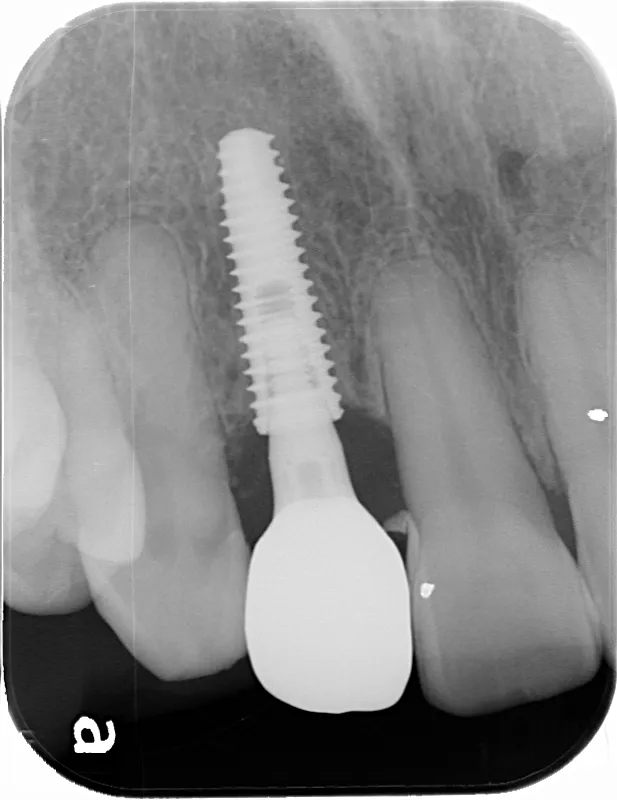

第一大臼歯1歯欠損をインプラントで回復したケースです。第一大臼歯は永久歯の中で一番最初に生える歯ですが、一番早く傷んでしまう歯でもあります。噛む力の60%を負担し噛み合わせの安定に大きく影響しますので、この歯が欠損すると噛み合わせに悪い影響を与えてしまいます。インプラントで治すことにより噛み合わせが安定するだけでなく、ブリッジのように隣在歯を削らないので天然歯の寿命を延ばすメリットもあります。